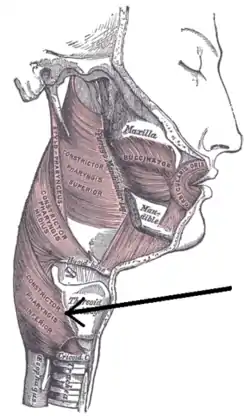

Muscles of the pharynx and cheek. (Constrictor pharyngis inferior visible at bottom left.) | |

The inferior pharyngeal constrictor muscle is a skeletal muscle of the neck. It is the thickest of the three outer pharyngeal muscles. It arises from the sides of the cricoid cartilage and the thyroid cartilage. It is supplied by the vagus nerve (CN X). It is active during swallowing, and partially during breathing and speech. It may be affected by Zenker's diverticulum.

The inferior pharyngeal constrictor muscle is composed of two parts. The first part (and more superior) arises from the thyroid cartilage (thyropharyngeal part), and the second part arises from the cricoid cartilage (cricopharyngeal part).[1]

- On the thyroid cartilage, it arises from the oblique line on the side of the lamina, from the surface behind this nearly as far as the posterior border and from the inferior horn of the thyroid cartilage.

- From the cricoid cartilage, it arises in the interval between the cricothyroid muscle in front, and the articular facet for the inferior horn of the thyroid cartilage behind.

From these origins, the fibers spread backward and medially to insert with the muscle of the opposite side into the fibrous pharyngeal raphe in the posterior median line of the pharynx. The thyropharyngeal part mainly uses type 2 fibres (anaerobic), while the cricopharyngeal part mainly uses type 1 fibres (aerobic).[2] Fibre type may change after birth.[3]

The inferior fibers are horizontal and continuous with the circular fibers of the esophagus; the rest ascend, increasing in obliquity, and overlap the middle pharyngeal constrictor muscle. The cricopharyngeal part is synonymous with the upper esophageal sphincter (UES), which controls the opening of the cervical esophagus.[4] It is sometimes referred to as the cricopharyngeal inlet.